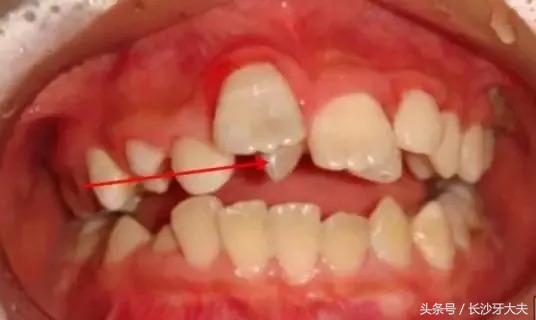

看完这些,大家对我有所了解了吧,正如上面所讲,如果是在替牙期,我的位置会阻碍正常新牙的萌出通道,导致对应恒牙的萌出位置发生异常,例如牙齿发生扭转、倾斜、拥挤或牙缝过大甚至不能萌出。

而且我奇怪的外形也会严重影响小主人的美观及心理健康;

讲了这么多,给大家看一例真实的案例吧:由于多生牙占据了正常门牙应在的位置,两颗门牙还没长出来就被迫分开了很大的距离。

只有去除多生牙的阻碍,以后才可以进行矫正排齐门牙,所以我还是摆脱不了被拔除的命运。